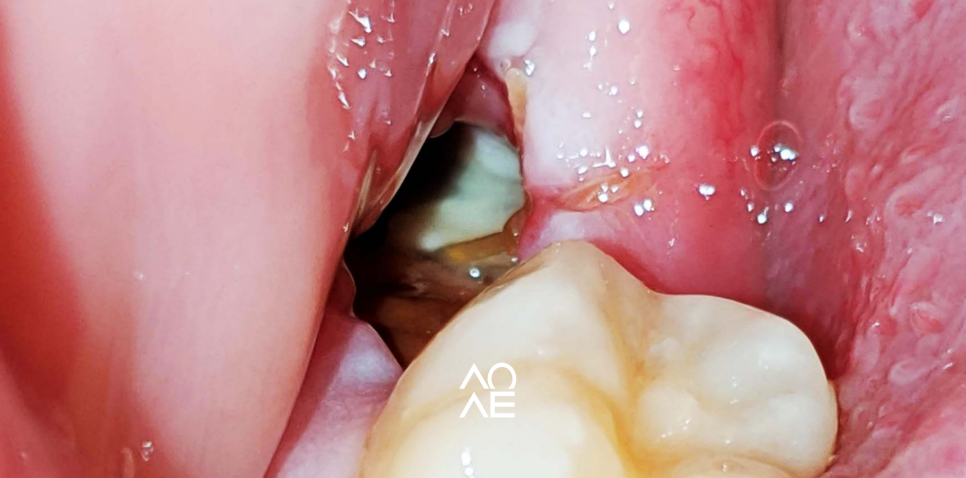

보자마자, 알 수 있었는데요

사랑니 발치 후에 발생할 수 있는

합병증인 "드라이소켓" 이라는

건성치조와 라 불리는 증상이었습니다

드라이소켓?

Dry Socket?

혈병이 떨어지거나 제대로 형성이 안되고

발치한 부위가 건조해지고

안쪽의 뼈가 세균에 노출되고

감염이 시작되면서 통증이 발생하죠